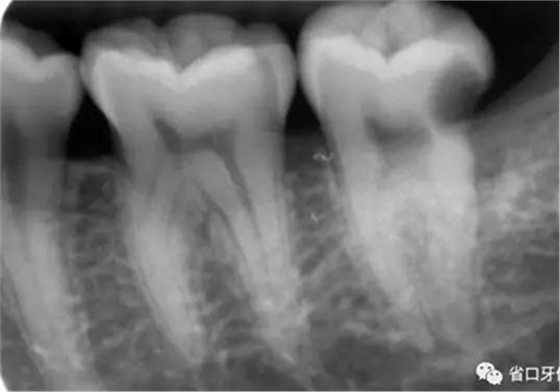

圖2 術(shù)前X片示遠(yuǎn)中鄰面牙體低密度影累及髓角